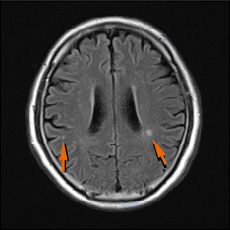

• 頭部MRI無症候性脳梗塞

無症候性脳梗塞